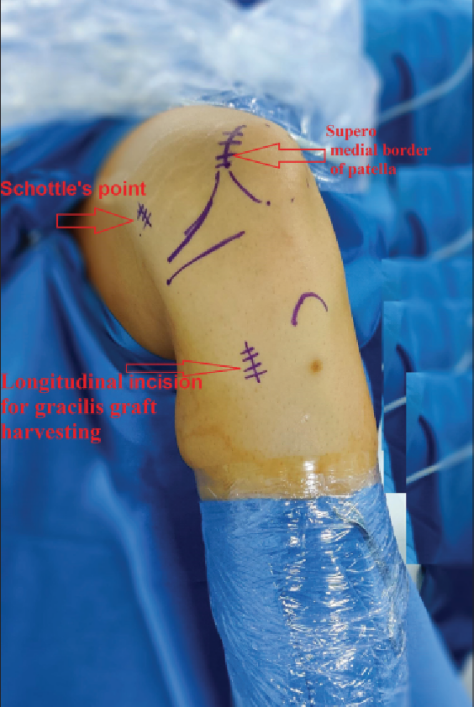

图1:一名27岁男性,其左膝关节出现复发性髌骨脱位。计划对他实施髌股内侧韧带重建术。在进行术区皮肤消毒和铺单后,标记出了相关解剖标志。箭头所指分别为舍特勒点、髌骨上内侧缘以及用于获取股薄肌移植物的纵向切口。

⑥然后,在透视下采用Schöttle技术,在导丝引导下于内收肌结节(AT)和股骨内上髁(MEC)中点前方的等长点处制作一个7毫米的骨隧道。等长点是在标准侧位平面上确定的,位于Blumensaat线后端点水平的近端、后皮质延长线前方1毫米处,以及股骨内侧髁后缘起点远端2.5毫米处。

④移植物股骨侧固定位置的选择:目前主要有术中透视或者由经验丰富的临床医师触摸找到 Schöttle 点。